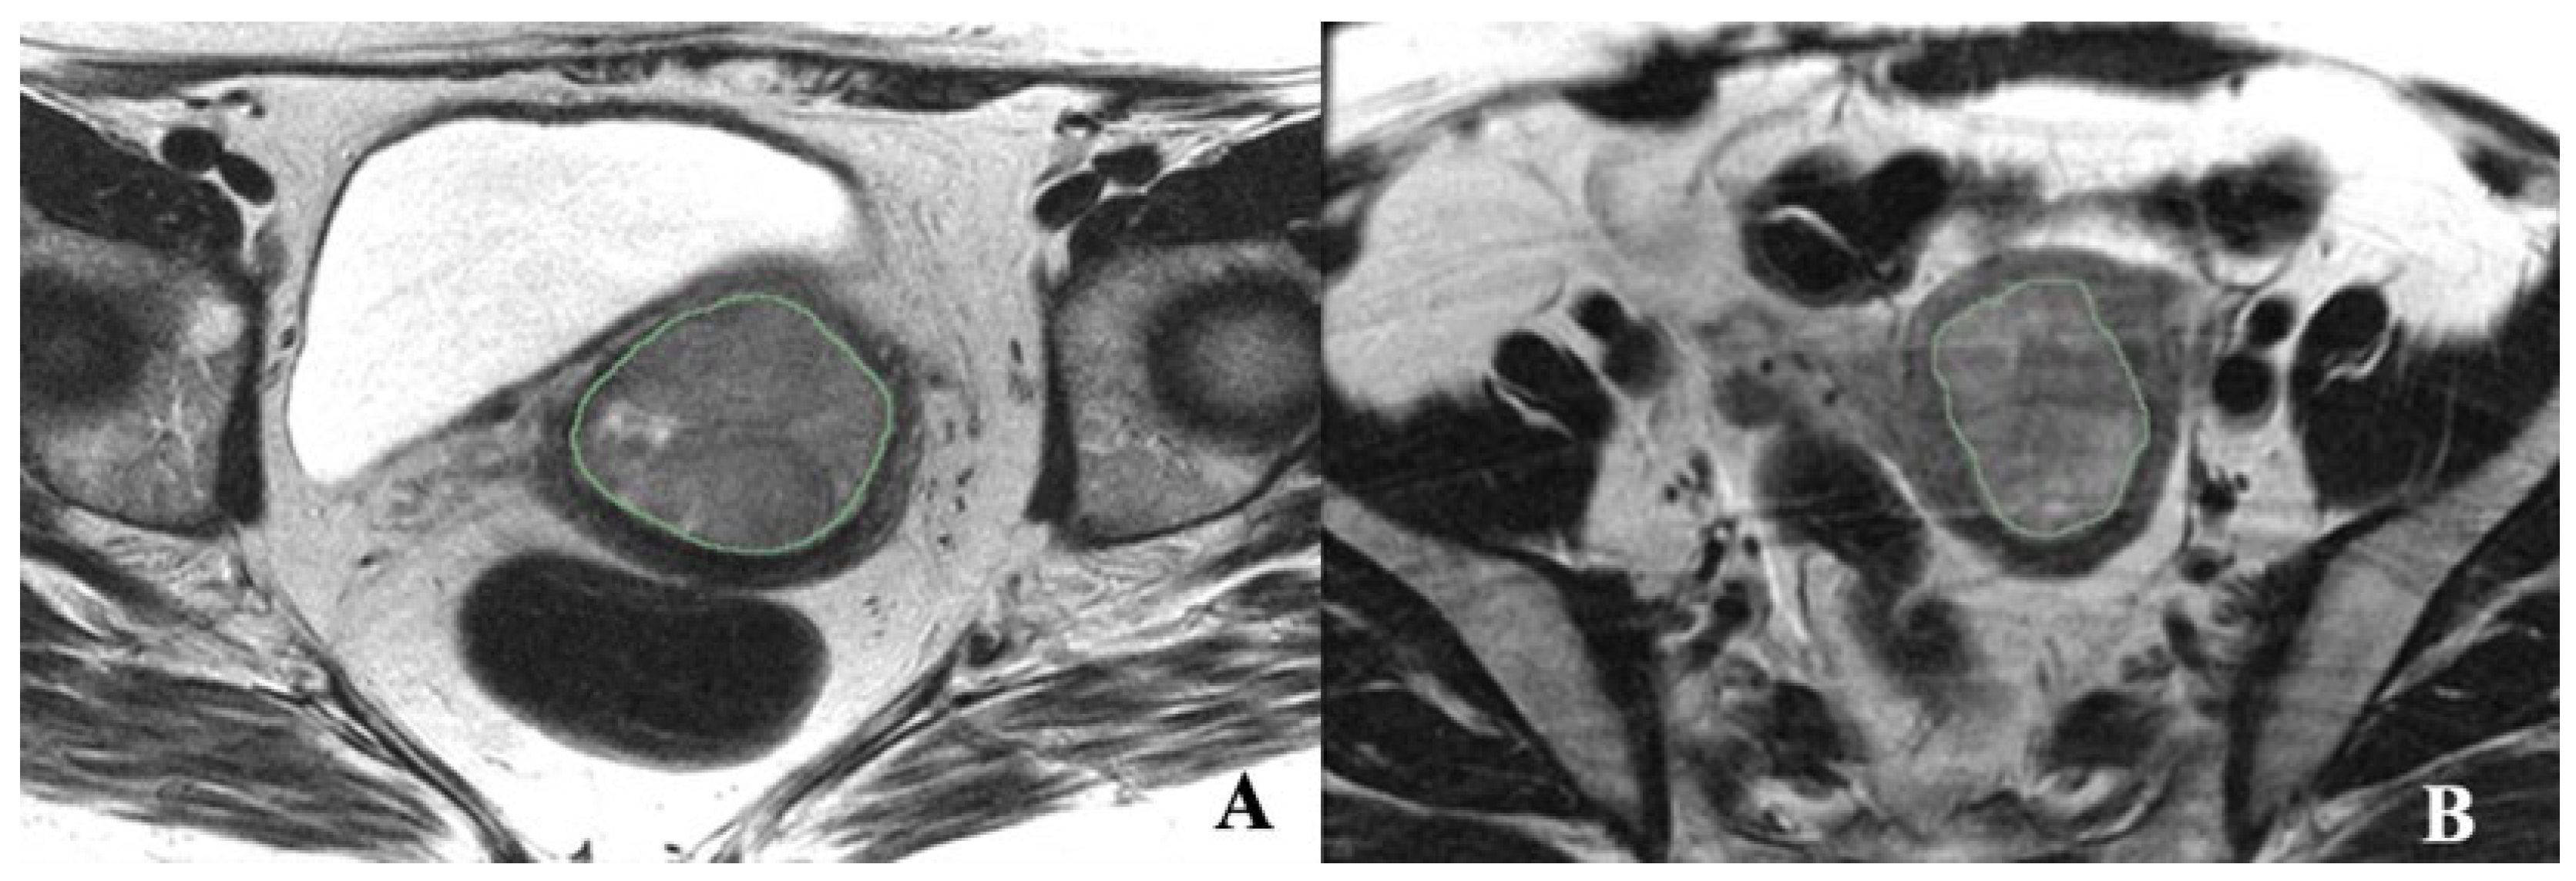

2.3. Tumor Segmentation and Radiomic Feature Extraction